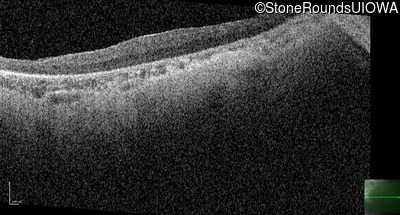

Optical Coherence Tomography - Left - 20/500 sc

Exemplar / OCT Stack

OCT Stack